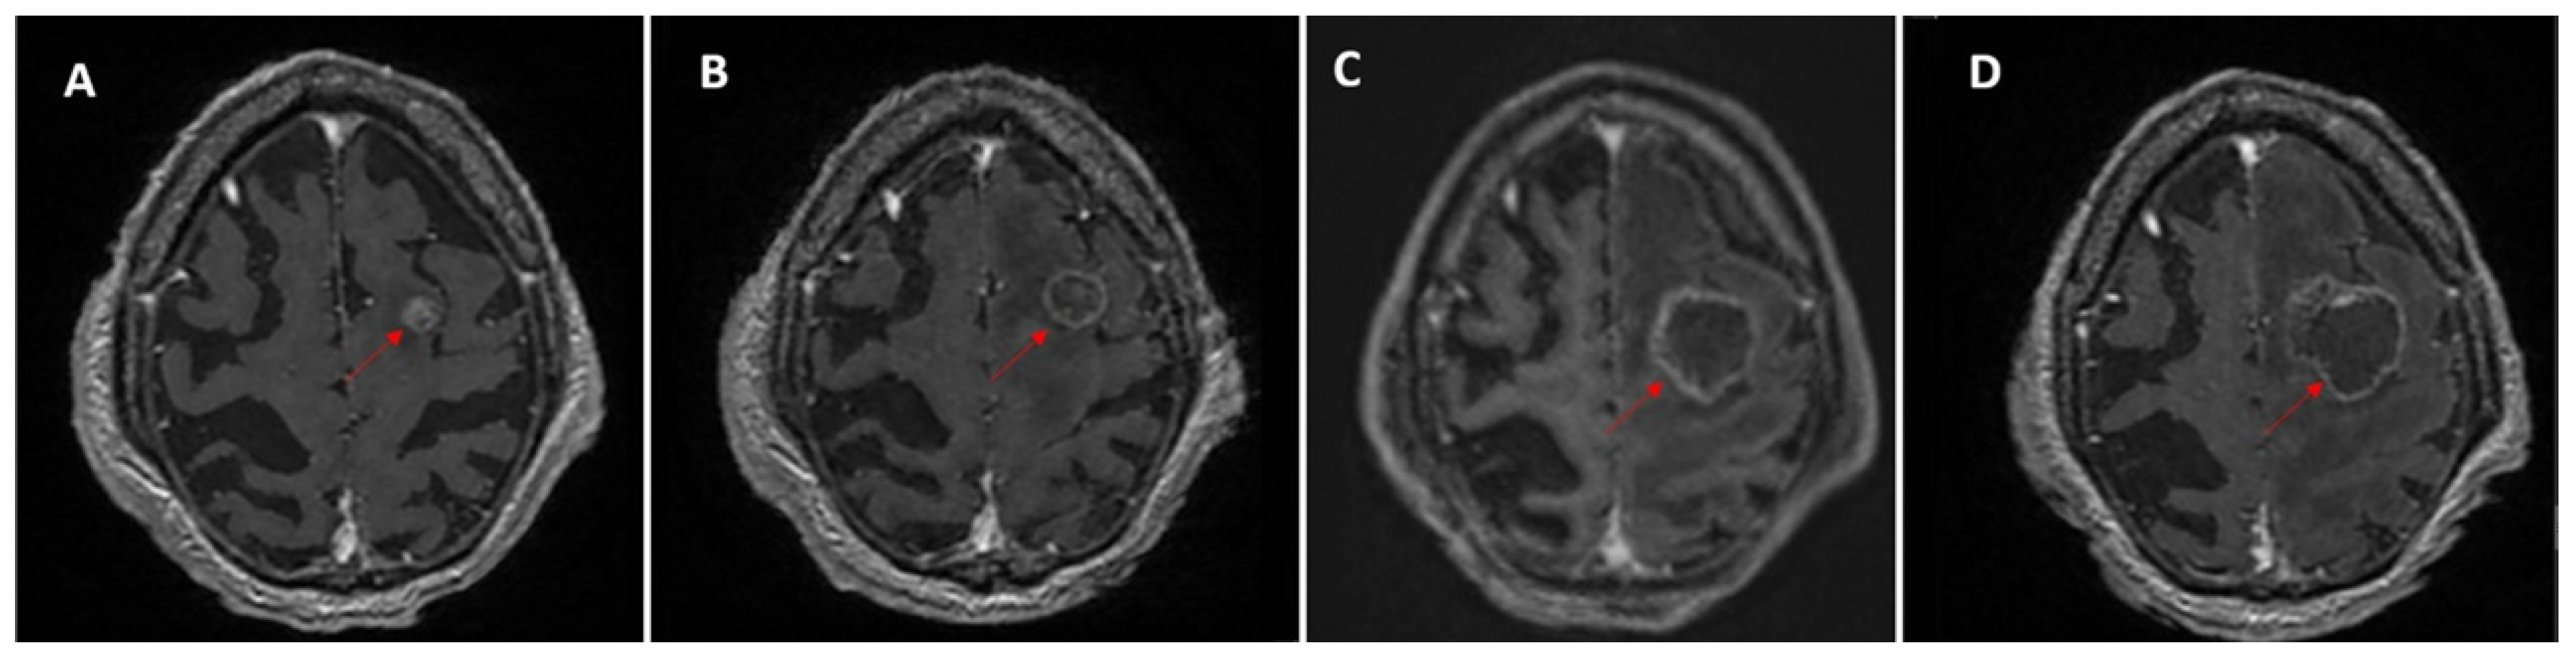

Figure 5. Longitudinal MRI follow-up of a patient with lung cancer and complex treatment history, showing brain metastases evolving in multiple “waves.” Each row illustrates a different lesion (AC). (Row (A)) A right temporal metastasis (red arrows) shows slight growth over the first three examinations, loss of enhancement at the fourth, followed by renewed enlargement and contrast uptake, along with the appearance of additional new metastases (yellow arrows). (Row (B)) A right lentiform nucleus lesion (red arrows) becomes more conspicuous on the third examination, subsequently regresses, and then shows renewed growth, remaining ambiguous between treatment effect (necrosis) and true progression. (Row (C)) A left cerebellar lesion (red arrows) visible on the third examination regresses after treatment. This case highlights the heterogeneity of longitudinal evolution, with coexisting progression, regression, and emergence of new lesions.

Lesions that remained stable (6.8%; 24/354) or showed regression (22.0%; 78/354) were typically previously treated but retained some degree of contrast enhancement. In clinical follow-up, these lesions may be more difficult to interpret when new metastases appear, particularly if their treated status or precise anatomical location is not explicitly documented in the report (Figure 5). Without consistent lesion-level tracking and explicit mention of prior treatment, residual post-treatment changes could be mistaken for newly developed or recurrent disease, contributing to potential reporting inconsistencies.